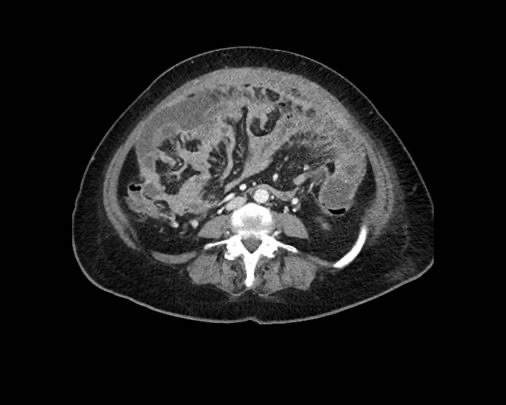

Hình ảnh

Hình ảnh CT của một bệnh nhân ung thư phúc mạc.

Một lượng nhỏ dịch cổ trướng hiện diện ở góc phần tư trước bên phải.

Các đường dày dạng nốt vuông góc với thành ruột được ghi nhận.

Hình ảnh này đại diện cho tổn thương xâm lấn mạc treo ruột lan rộng (mũi tên).